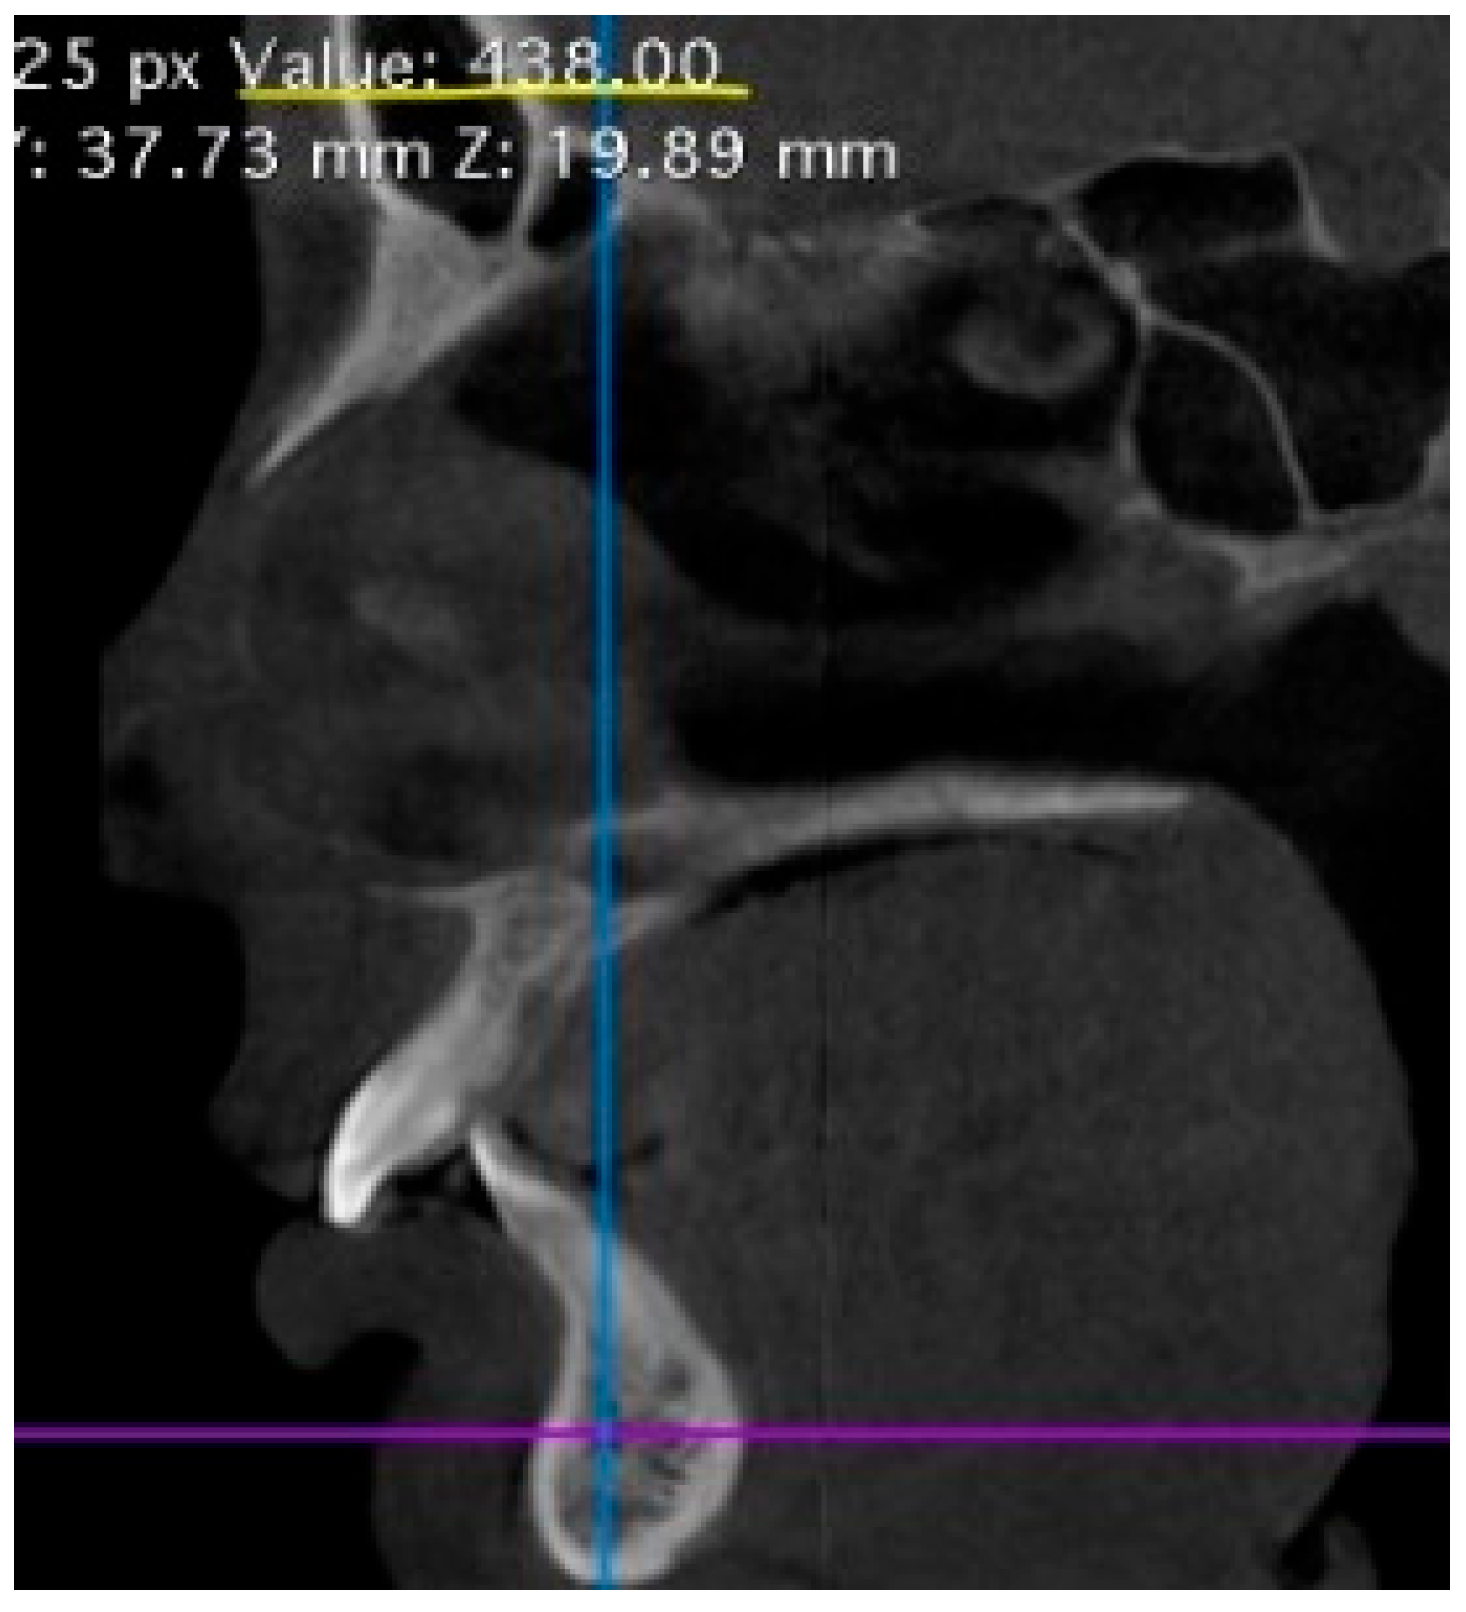

3.2. Radiological Bone Density of the Jaws, Hounsfield Index Analysis

| Sections of the Jaw | Group 1 (n = 19), HU | Group 2 (n = 19), HU | Group 3 (n = 19), HU | Group 4 (n = 19), HU |

|---|---|---|---|---|

| Anterior mandible | 2790 [2200; 3010] 1,3 | 989.0 [940.0; 1122] 1,3,4 | 1749 [1570; 1999] 1,2,4 | 3096 [1980; 3554] 2,3 |

| Posterior mandible | 1560 [1200; 1770] 2,3 | 785.0 [690.0; 916.0] 1,4 | 850.0 [790.0; 940.0] 1,4 | 1800 [1384; 1960] 2,3 |

| Anterior maxilla | 534.5 ± 123.4 | 476.3 ± 71.3 4 | 460.5 ± 66.2 4 | 614.6 ± 171.7 2,3 |

| Posterior maxilla | 378.9 ± 91.0 2 | 207.9 ± 19.4 1,3,4 | 302.5 ± 104.7 2,4 | 432.5 ± 114.6 2,3 |